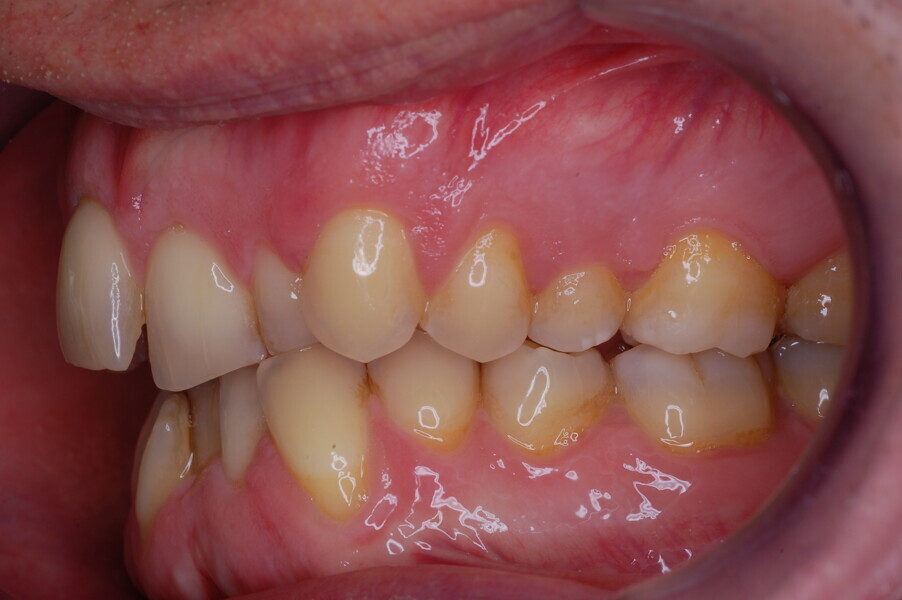

A healthy 39-year-old man presented to our orthodontic office with the chief complaint of an unattractive dental appearance and fear of the orthognathic surgery proposed by another orthodontist. Clinically, the patient’s profile was straight, and the frontal view did not show any facial asymmetry. The functional examination did not reveal any mandibular deviation or reduced movements. The patient had no joint pain, and no joint noise was observed.

Figs. 1–8: Pretreatment facial and intra-oral photographs.

From the periodontal point of view, the patient showed a good attitude to oral hygiene, but crowding of the mandibular incisors made cleaning difficult in that area, causing plaque accumulation and localised gingival inflammation. The panoramic radiograph revealed the presence of the mandibular third molars and confirmed the absence of the mandibular right central incisor (Fig. 10).

The cephalometric analysis showed a skeletal Class II malocclusion (convexity of Point A: 4.9 mm), a slightly retruded chin position (facial depth: 78.1°) and a skeletal open bite tendency (lower facial height: 53.19°; facial axis: 80.58°; Fig. 9). The mandibular incisors were lingually tipped (Li–APog: 9.3°) and retruded (Li–APog: 1.55 mm), and there was an increased inter-incisal angle of 142.9°.